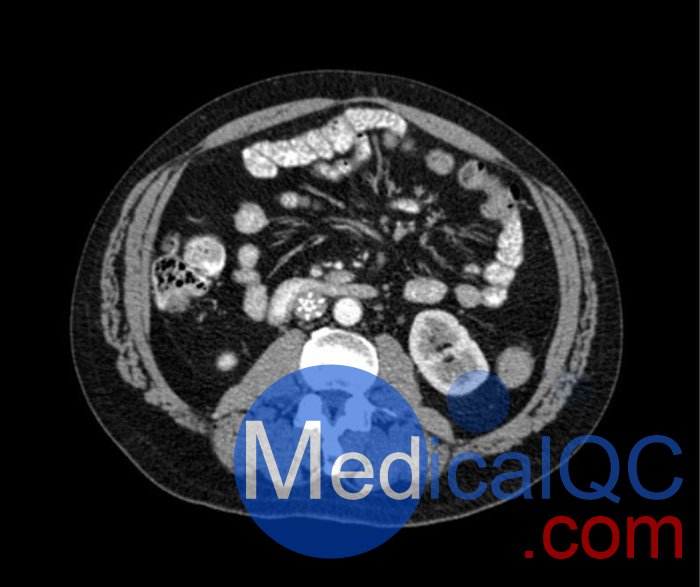

WEK53-04肝硬化腹部模體,WEK53-04門靜脈期腹部模體詳細(xì)介紹:

WEK53-04肝硬化腹部模體,WEK53-04腹部模體模擬了門靜脈期的造影劑增強(qiáng)腹部。它覆蓋了第十胸椎至第三腰椎。

WEK53-04肝硬化腹部模體,WEK53-04腹部模體代表膽囊切除術(shù)后的腹部,帶有小夾子。肝臟有肝硬化的典型體征,在第三腰椎水平植入下腔靜脈過濾器。兩個(gè)腎臟都有囊性病變,左側(cè)有一小塊腎結(jié)石。

該模型可用于 CT(包括 CBCT)以評(píng)估和優(yōu)化成像性能和后處理應(yīng)用,包括支持 AI 的應(yīng)用。它也適用于培訓(xùn)目的。

該模型提供了對(duì)軟組織和骨組織的詳細(xì)而逼真的模擬??障吨刑畛渲s-160HU的纖維素-聚合物復(fù)合材料。

WEK53-04肝硬化腹部模體,WEK53-04門靜脈期腹部模體診斷特征

真實(shí)模擬脈管系統(tǒng)、骨骼和軟組織,包括肝臟、胰腺、脾臟、腎上腺、腎臟、胃、小腸和結(jié)腸。

• 肝硬化

• 膽囊切除術(shù)

• 下腔靜脈濾器

• 腎囊腫

• 腎結(jié)石

• 淋巴結(jié)腫大

WEK53-04肝硬化腹部模體,WEK53-04門靜脈期腹部模體產(chǎn)品成像圖: